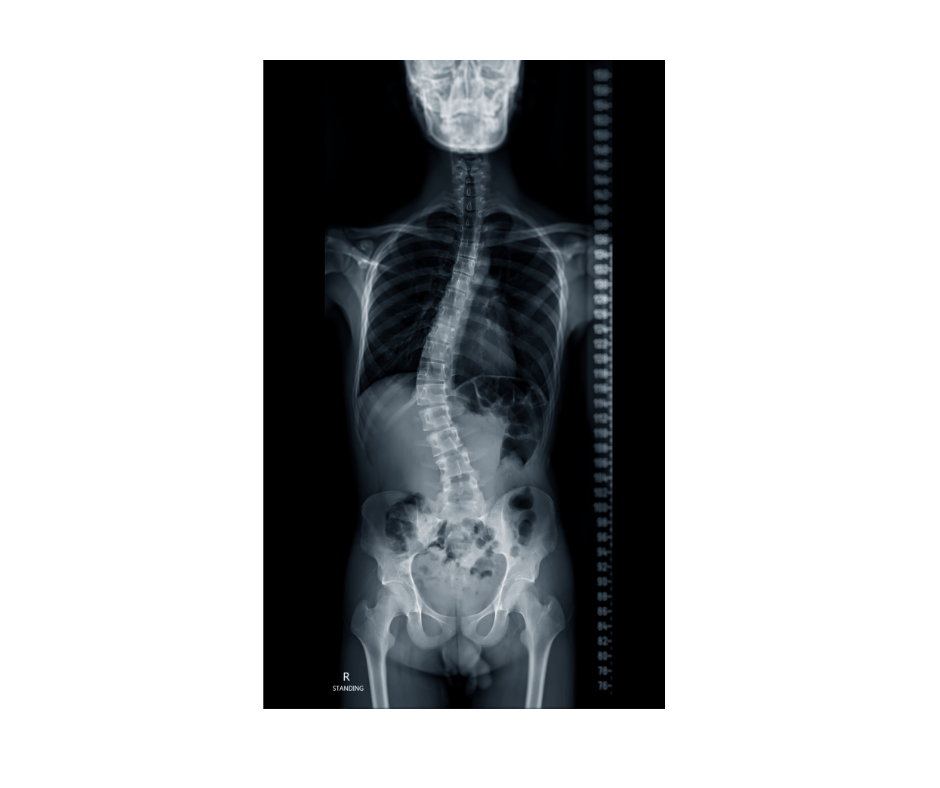

Living with scoliosis can bring challenges such as back pain, uneven posture, and limited mobility. But beyond the physical, scoliosis often affects how people feel about themselves. Changes in body shape, posture, or wearing a brace during formative years can deeply impact self-esteem and emotional health.

Yoga therapy offers a holistic, compassionate way to manage scoliosis, addressing both the body and the mind. Through mindful movement and exercises tailored to your unique curve, soft tissue release, breathwork, and self-awareness practices, you’ll not only find physical relief but also build confidence, resilience, and a deeper acceptance of your body.

Personalized practices tailored to different scoliosis patterns (C-curve, S-curve, thoracic, lumbar).